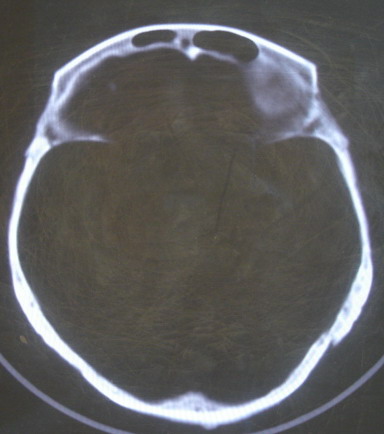

标题: CT13146:是骨折吗?请各位指教

女 63岁 左额部碰伤

现有资料未见骨折表现

左枕部颅缝略增宽并轻度错位,建议结合临床,必要时复查

左额部未见明确骨折

左侧颞枕部颅缝分离骨折可疑。建议结合临床,必要时复查。

都错位了,当然是报骨折了。

左侧颞枕部颅缝分离骨折可疑。

结合临床,排除左侧颞枕部颅缝分离骨折可能。